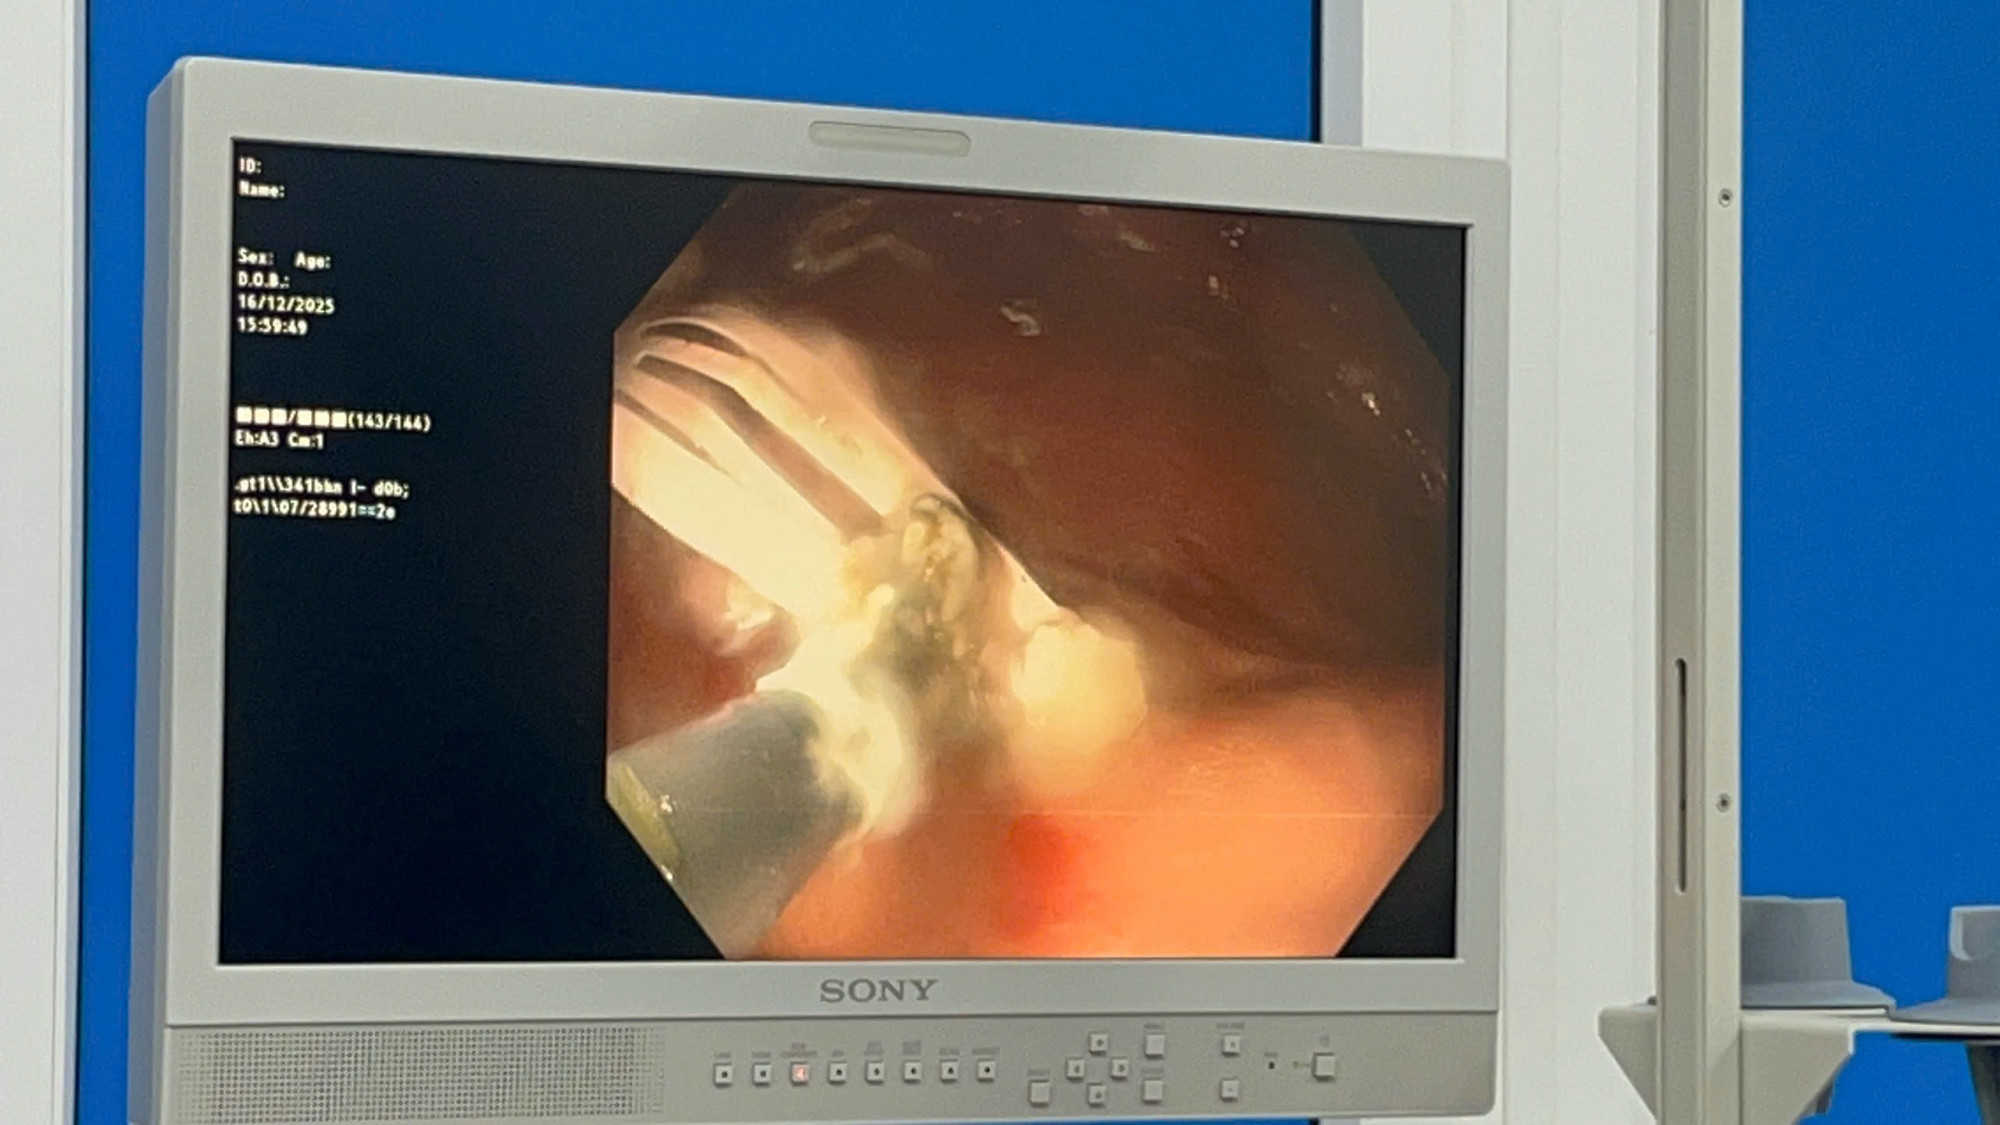

PNO - Ngày 16/12, Bệnh viện Sản - Nhi tỉnh Quảng Ngãi tiếp nhận cấp cứu bệnh nhi T.V.K.N (6 tuổi), ở xã Sơn Tịnh, nhập viện do nuốt phải kẹp tóc bằng kim loại.